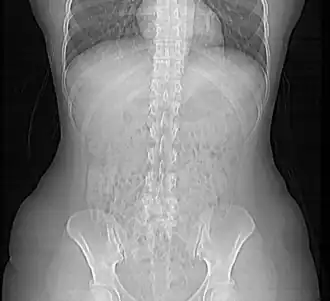

In de gezondheidszorg, met name binnen de radiologieafdeling van een ziekenhuis, wordt op grote schaal gebruikgemaakt van medische beeldvormende systemen (bijvoorbeeld röntgen, CT, MRI en echografie). De beelden worden aangemaakt door beeldvormende modaliteiten en uiteindelijk in beeldarchieven (PACS systemen) opgeslagen. De gegevensuitwisseling tussen deze systemen vindt plaats door middel van het uitwisselen van elektronische berichten. De structuur van die berichten wordt gedefinieerd door standaarden zoals DICOM. Naast DICOM wordt in de gezondheidszorg eveneens gebruikgemaakt van onder andere de HL7- en EDIFACT-EDI-standaarden.